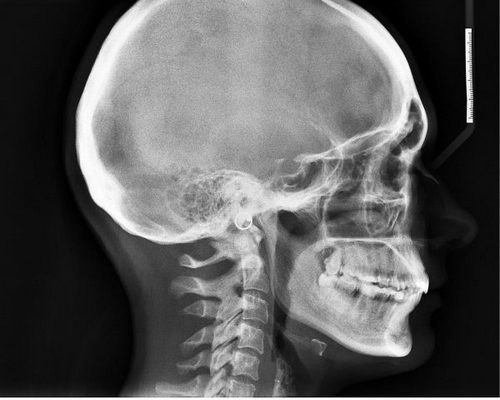

Она может быть и последствием травм и ранений черепа, головного мозга, когда из-за ушиба нарушается отток жидкости из полостей желудочков мозга, возникает повышенное внутричерепное давление, нарушается приток-отток крови. Следствие – головные боли.

Очень сильные головные боли могут быть признаком растущей опухоли головного мозга и нередко сопровождаются потерей сознания, двоением в глазах, рвотой. Это происходит за счет сдавливания опухолью сосудов и полостей желудочка мозга.

Головная боль может быть вызвана приступом мигрени (с французского «мигрень» переводится как «половина головы») . Причем приступ, как правило, захватывает либо правую, либо левую часть головы. Иногда боль перемещается из одной половины в другую и очень редко распространяется на всю голову. Обычно приступ начинается с потемнения в глазах, мелькания «мушек» , геометрических фигур и даже «молний» . Затем появляется невыносимая пульсирующая боль в половине головы. Она часто сопровождается головокружением, общим недомоганием, тошнотой, рвотой, которая, правда, немного облегчает состояние.